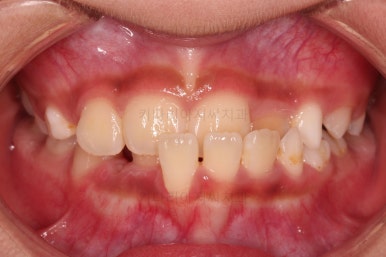

부산어린이교정 초진 시 얼굴 모습인데요.

아랫 입술 부위가 앞으로 많이 나와 있어 주걱턱의 느낌을 주고요.

웃거나 말할 때 아래 앞니가 앞에 튀어나와 있어 심미적으로도 좋지 못하죠.

반대교합이 주로 좌측 앞니쪽에서 있다보니 해당 부위로 아래턱이 밀리면서 앞모습에서 비대칭도 보입니다.